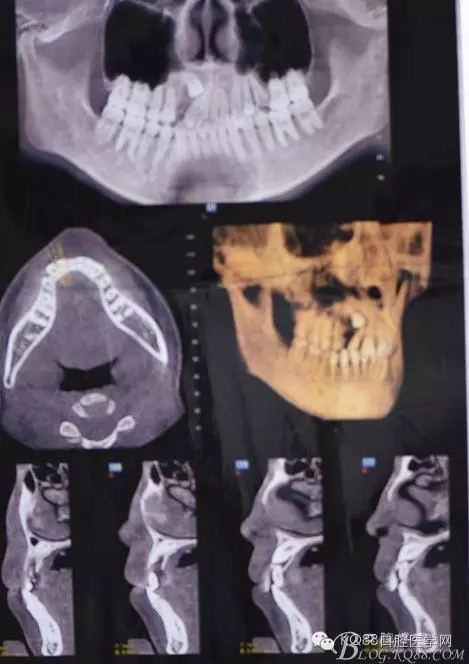

圖1.術(shù)前的cbct檢查:13位于12遠(yuǎn)中根尖區(qū),13牙根接近上頜竇、53牙根滯留。